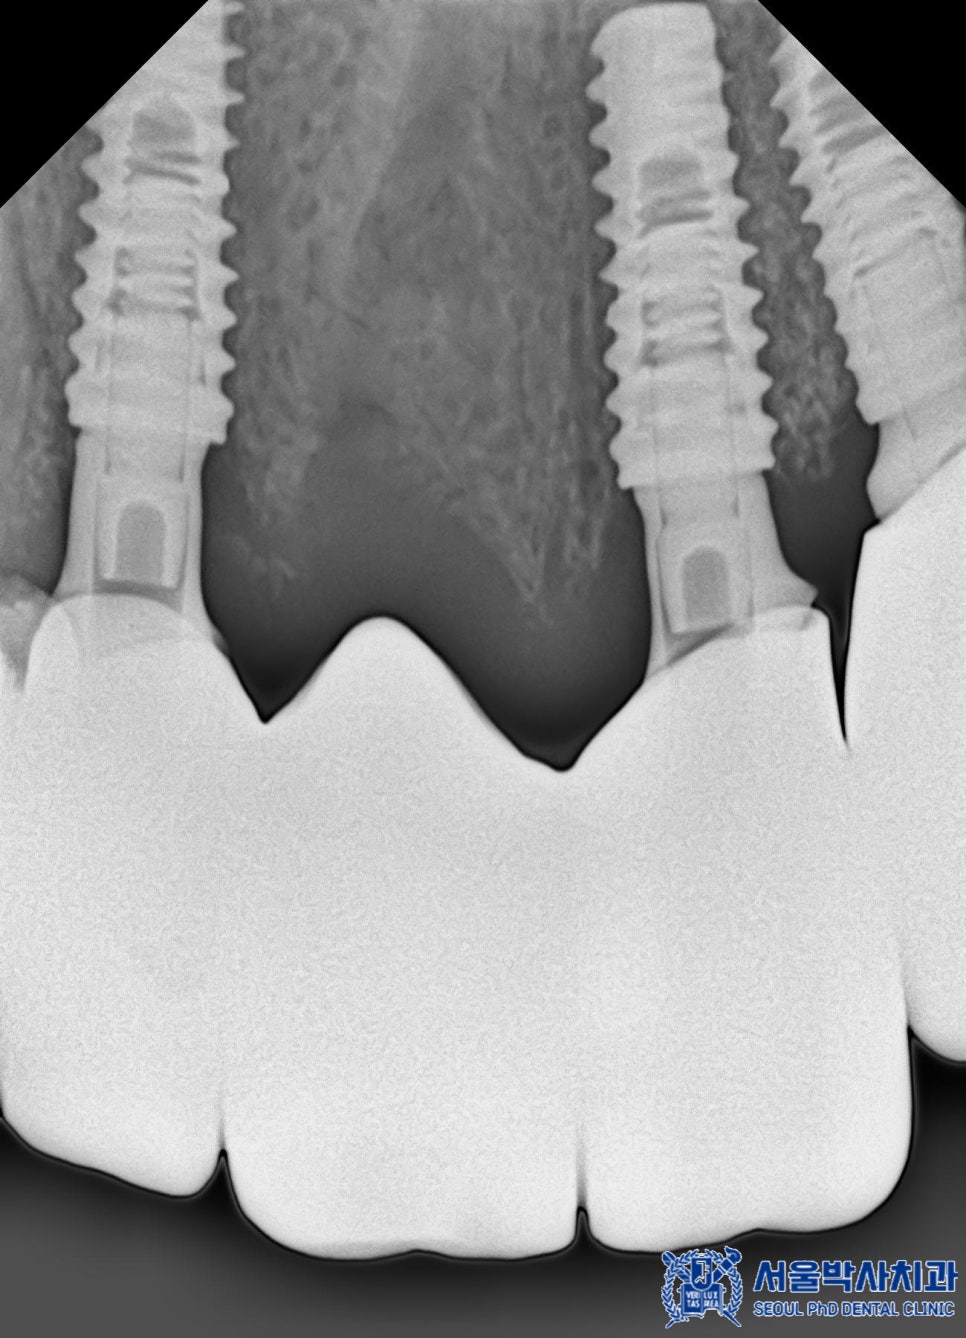

무절개 임플란트는 컴퓨터 분석을 통해

미리 계획된 경로를 따라 식립하기 때문에

절개가 필요하지 않고 출혈이 적으며

회복 속도가 빠릅니다.

또한, 위 사진처럼

수술가이드를 제작하여 오차 없이

정밀한 위치에 임플란트를

심을 수 있기 때문에

성공률도 높아지게 됩니다.